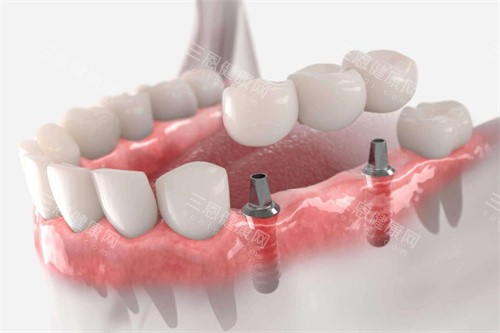

缺牙修復怎麼選?種植、活動、吸附性義齒對比的核心是使用感受。種植牙像真牙一樣紮根在牙槽骨裏,吃飯時不用取,嚼東西有力,啃蘋果、吃排骨都沒問題,和自然牙的使用感比較接近;

活動義齒要每天取下來清潔,吃飯時容易晃,咬硬東西會漏食物,使用感稍差;吸附性義齒不用取戴,靠吸附力貼緊牙齦,吃飯比活動義齒穩,比種植牙稍軟,缺牙修復怎麼選?種植、活動、吸附性義齒對比的使用感受,決定了日常體驗。

很多人用活動義齒後,因為吃飯漏食物,慢慢不敢吃硬的,而種植牙能避免這種情況,吸附性義齒則適合想避免取戴麻煩,又沒預算種牙的人,缺牙修復怎麼選?種植、活動、吸附性義齒對比的使用感受,是選修複方式的重要參考。